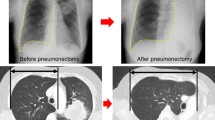

None of the animals included in this study had surgery-related death or comorbidity. The representative images of each group and the time course of lung volume measured from the CT data are shown in Fig. 1a and b, respectively. Lung volumes at 6 months post-surgery in the Sham, Bilobectomy, and Pneumonectomy groups were 582.5 ± 55.3 ml, 791.8 ± 102.4 ml, and 1100.8 ± 238.1 ml, respectively. Furthermore, the increase rates were 4.7 ± 7.5%, 26.2 ± 11.3%, and 73.5 ± 5.2%, respectively. The rates of increase were significantly higher in the Pneumonectomy group than in the other two groups (p < 0.001, each), and the increase rates in the Bilobectomy group were significantly higher than that in the Sham group (p = 0.004). For comparison, the values of radiologic lung volume of the left and right lungs in each canine 6 months after surgery are presented in Fig. 1c.

(a) Representative computed tomography (CT) images 6 months after surgery of the Pneumonectomy, Bilobectomy, and Sham groups. (Window level: − 600, window width: 1500. Reconstruction kernel: FC13. Reconstructed slice thickness: 1 mm.) (b) The time course of lung volume measured from CT images. (c) The values of radiologic lung volume of the left and right lungs in each canine at 6 months after surgery. Bi: Bilobectomy, PNX: Pneumonectomy.